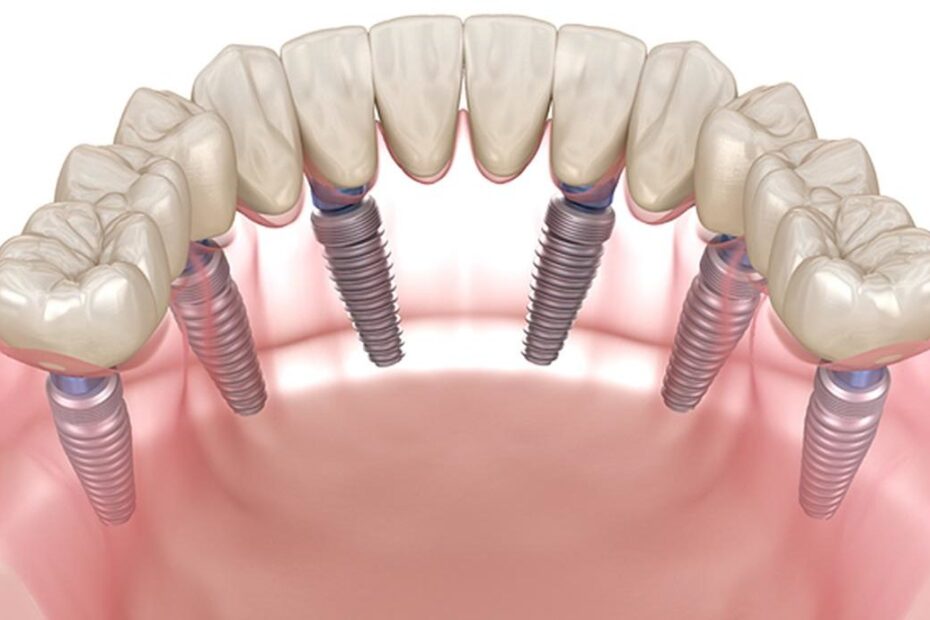

All-on-6 («всё на шести») — это инновационный протокол одноэтапной имплантации, при котором полная несъемная зубная конструкция фиксируется всего на 6 титановых имплантатах. Это усовершенствованная и более стабильная методика для сложных случаев, где костной ткани может быть недостаточно для других видов протезирования.

Шесть имплантатов создают надежную опору, равномерно распределяющую жевательную нагрузку. Это как фундамент дома: чем он прочнее, тем долговечнее вся конструкция. Такой подход позволяет часто избежать сложной и дорогостоящей операции по наращиванию костной ткани (синус-лифтинга).

- Установка имплантатов: В день операции с использованием хирургического шаблона точно и минимально инвазивно устанавливаем 6 имплантатов.